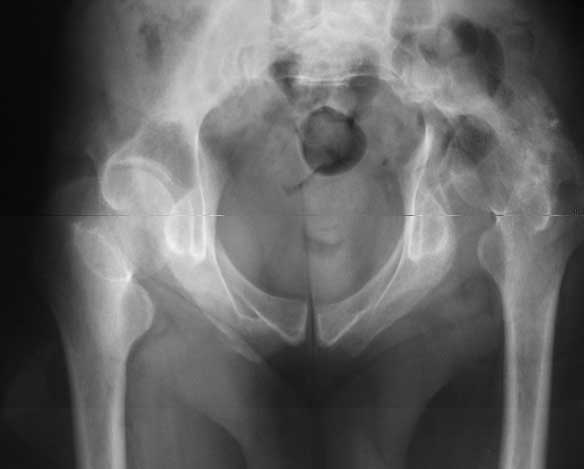

Dear All, The patient came to us for opinion regarding this # of pelvis which he sustained 5 months back.

He gives history of being on skin traction for 3,5months. After that he was advised partial weight bearing to be graduated to full weight bearing. Now the patient has difficulty in weight bearing as it is painful. He can walk a few steps only with the help of a walker. Hip movements are restricted and painful. Fl-90* ER-10* IR-0, shortening-4cm. He also had # of humerus and radius/ulna, which were plated and have united. The serial x-rays of the pelvis/Hip during these 5 months show that the hip joint has been in the same position. I have the CT pictures also but not digitalized as yet.

He is 47 years old, Class-1 officer.What are the options? Expert comments please.1. # Pelvis stabilization - Is it possible at 6 mths? And subsequently THR.

2. THR in this position- Cup positioning in a deformed pelvis?

It is a displaced and ununited fracture of the acetabulum, probably type C (AO). The pelvis is not fractured from what one can see of the sacro iliac joint.

Sorry missed the wide open pubic diastasis.